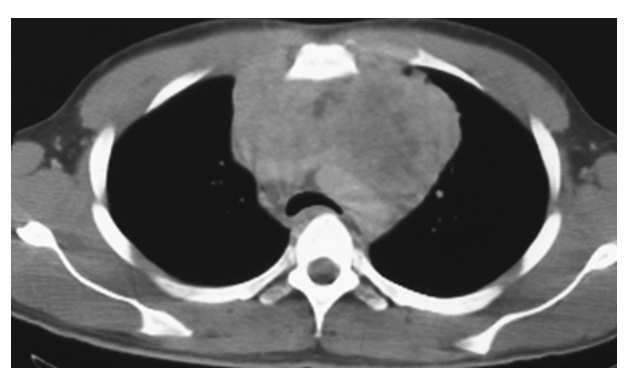

Pericardial Effusion. Contrast-enhanced CT (CECT) shows increased fluid density around the heart consistent with a pericardial effusion.

Pericardial Effusion. Normal for comparison.